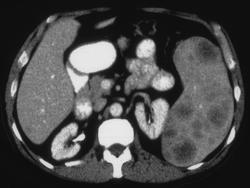

Splenic Laceration W/bleed